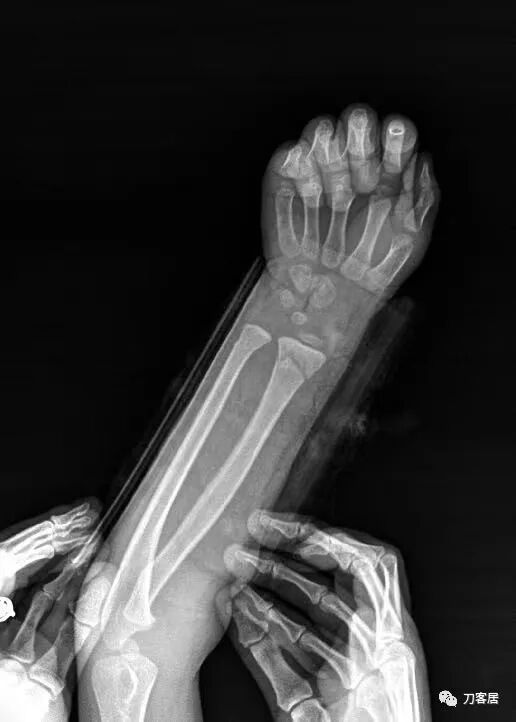

2021年7月21日,在中华骨科网儿童骨科病例讨论群里,看到了几张图片,是某仁慈医院的一位手外科医生做的手术,被某地器械厂家发在朋友圈里炫耀,有小儿骨科医生看不过去,就发群里请大家评论,引起众多小儿骨科医生的批评。

下面是这个6岁孩子,尺桡骨远端双骨折的术前及术后片子和外观照片。

1.  这是一个很简单的6岁儿童无移位的尺桡骨远端骨折。没有皮肤损伤,没有移位,没有骨折碎块儿。

2.  这个骨折处理起来也很简单,单纯的打石膏托或者中医的小夹板,或者正规的包括腕关节和肘关节的管型石膏外固定4周即可治愈该骨折。实在不行,如果这个孩子比较听话,不太调皮的话,用一本书,一个三角巾悬吊固定4周,都可以治愈该骨折。但是给这个患者用外固定架做了手术,而且桡骨远端的几颗克氏针距离骨折线太近,其中一枚克氏针进入到骨折间隙内。从这个术中图片来看,术者的外固定手术技术也有待于进一步的提高。毕竟术者应该还很年轻。从X线片来看,前臂及手的尺侧有不透光影,应该还使用了外固定石膏绷带托,而且我猜测应该是高分子的石膏绷带托,这个是纯属猜测,不一定是对的,不过如何解释前臂尺侧的不透光影呢?如果真是用了石膏绷带外固定的话,那为啥要做手术呢?外固定架术后就不该再用石膏绷带托辅助了。